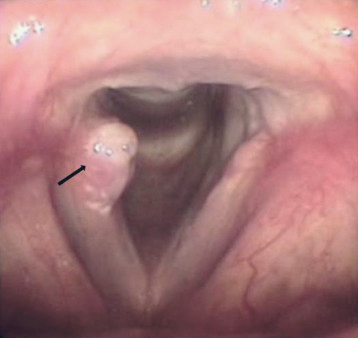

역류성 식도염으로 속이 쓰릴 때 흉골 뒤쪽의 가슴에서 타는 듯한 느낌이 들며, 위의 구덩이에서 시작해 목 뒤 쪽으로 빠르게 상승합니다. 이 통증은 목과 팔 뼈의 중심부로 이어질 수 있는데, 식도염이 의심되면 상부 소화관 내시경 검사를 받아야 하는 이유입니다.